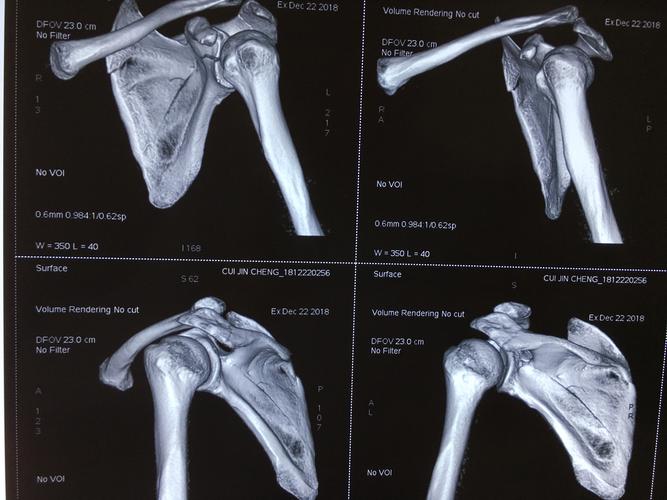

肩胛骨关节盂骨折

肩胛骨关节盂骨折,骨关节炎膝关节畸形

喙突联合1/5关节盂被喙锁韧带,喙肩韧带牵拉向前上形成一个撕脱骨折

一例肩胛盂骨折肩关节镜下骨折内固定术

电击伤致双侧肩胛骨及肱骨头骨折病例分析

肩盂骨折

来源:新乡医学影像 1 肩关节盂环形骨骺约6岁开始化骨.